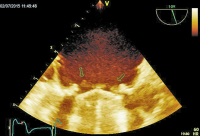

TEE

Abbildung 5: Rezidivendokarditis mit Vegetationen an der Mitralklappenprothese.